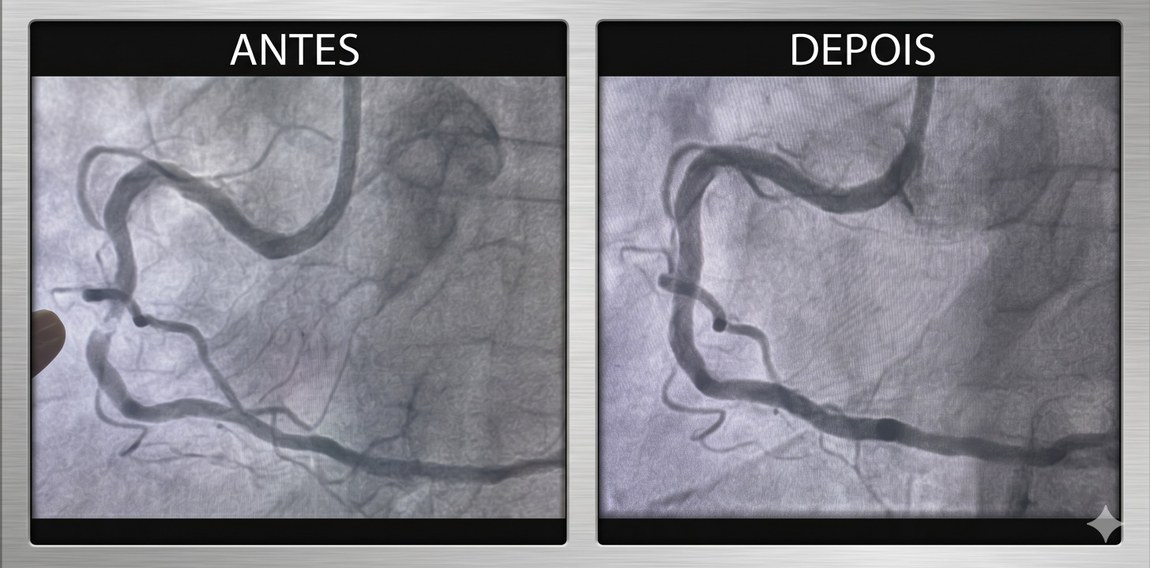

Realizado pelos cardiologistas intervencionistas Thiago Lisboa e Glauco Gusmão, o procedimento atendeu um paciente que apresentava dor torácica e falta de ar limitantes, com importante impacto na qualidade de vida. O cateterismo cardíaco evidenciou uma obstrução de 90% em uma artéria coronária, associada a uma placa extremamente calcificada (descrita como um verdadeiro "bloco de cálcio", conforme evidenciado nas imagens do exame), cenário em que as técnicas convencionais de angioplastia apresentam maior limitação técnica. Após o procedimento realizado com sucesso, o paciente recebeu alta hospitalar em menos de 24 horas.